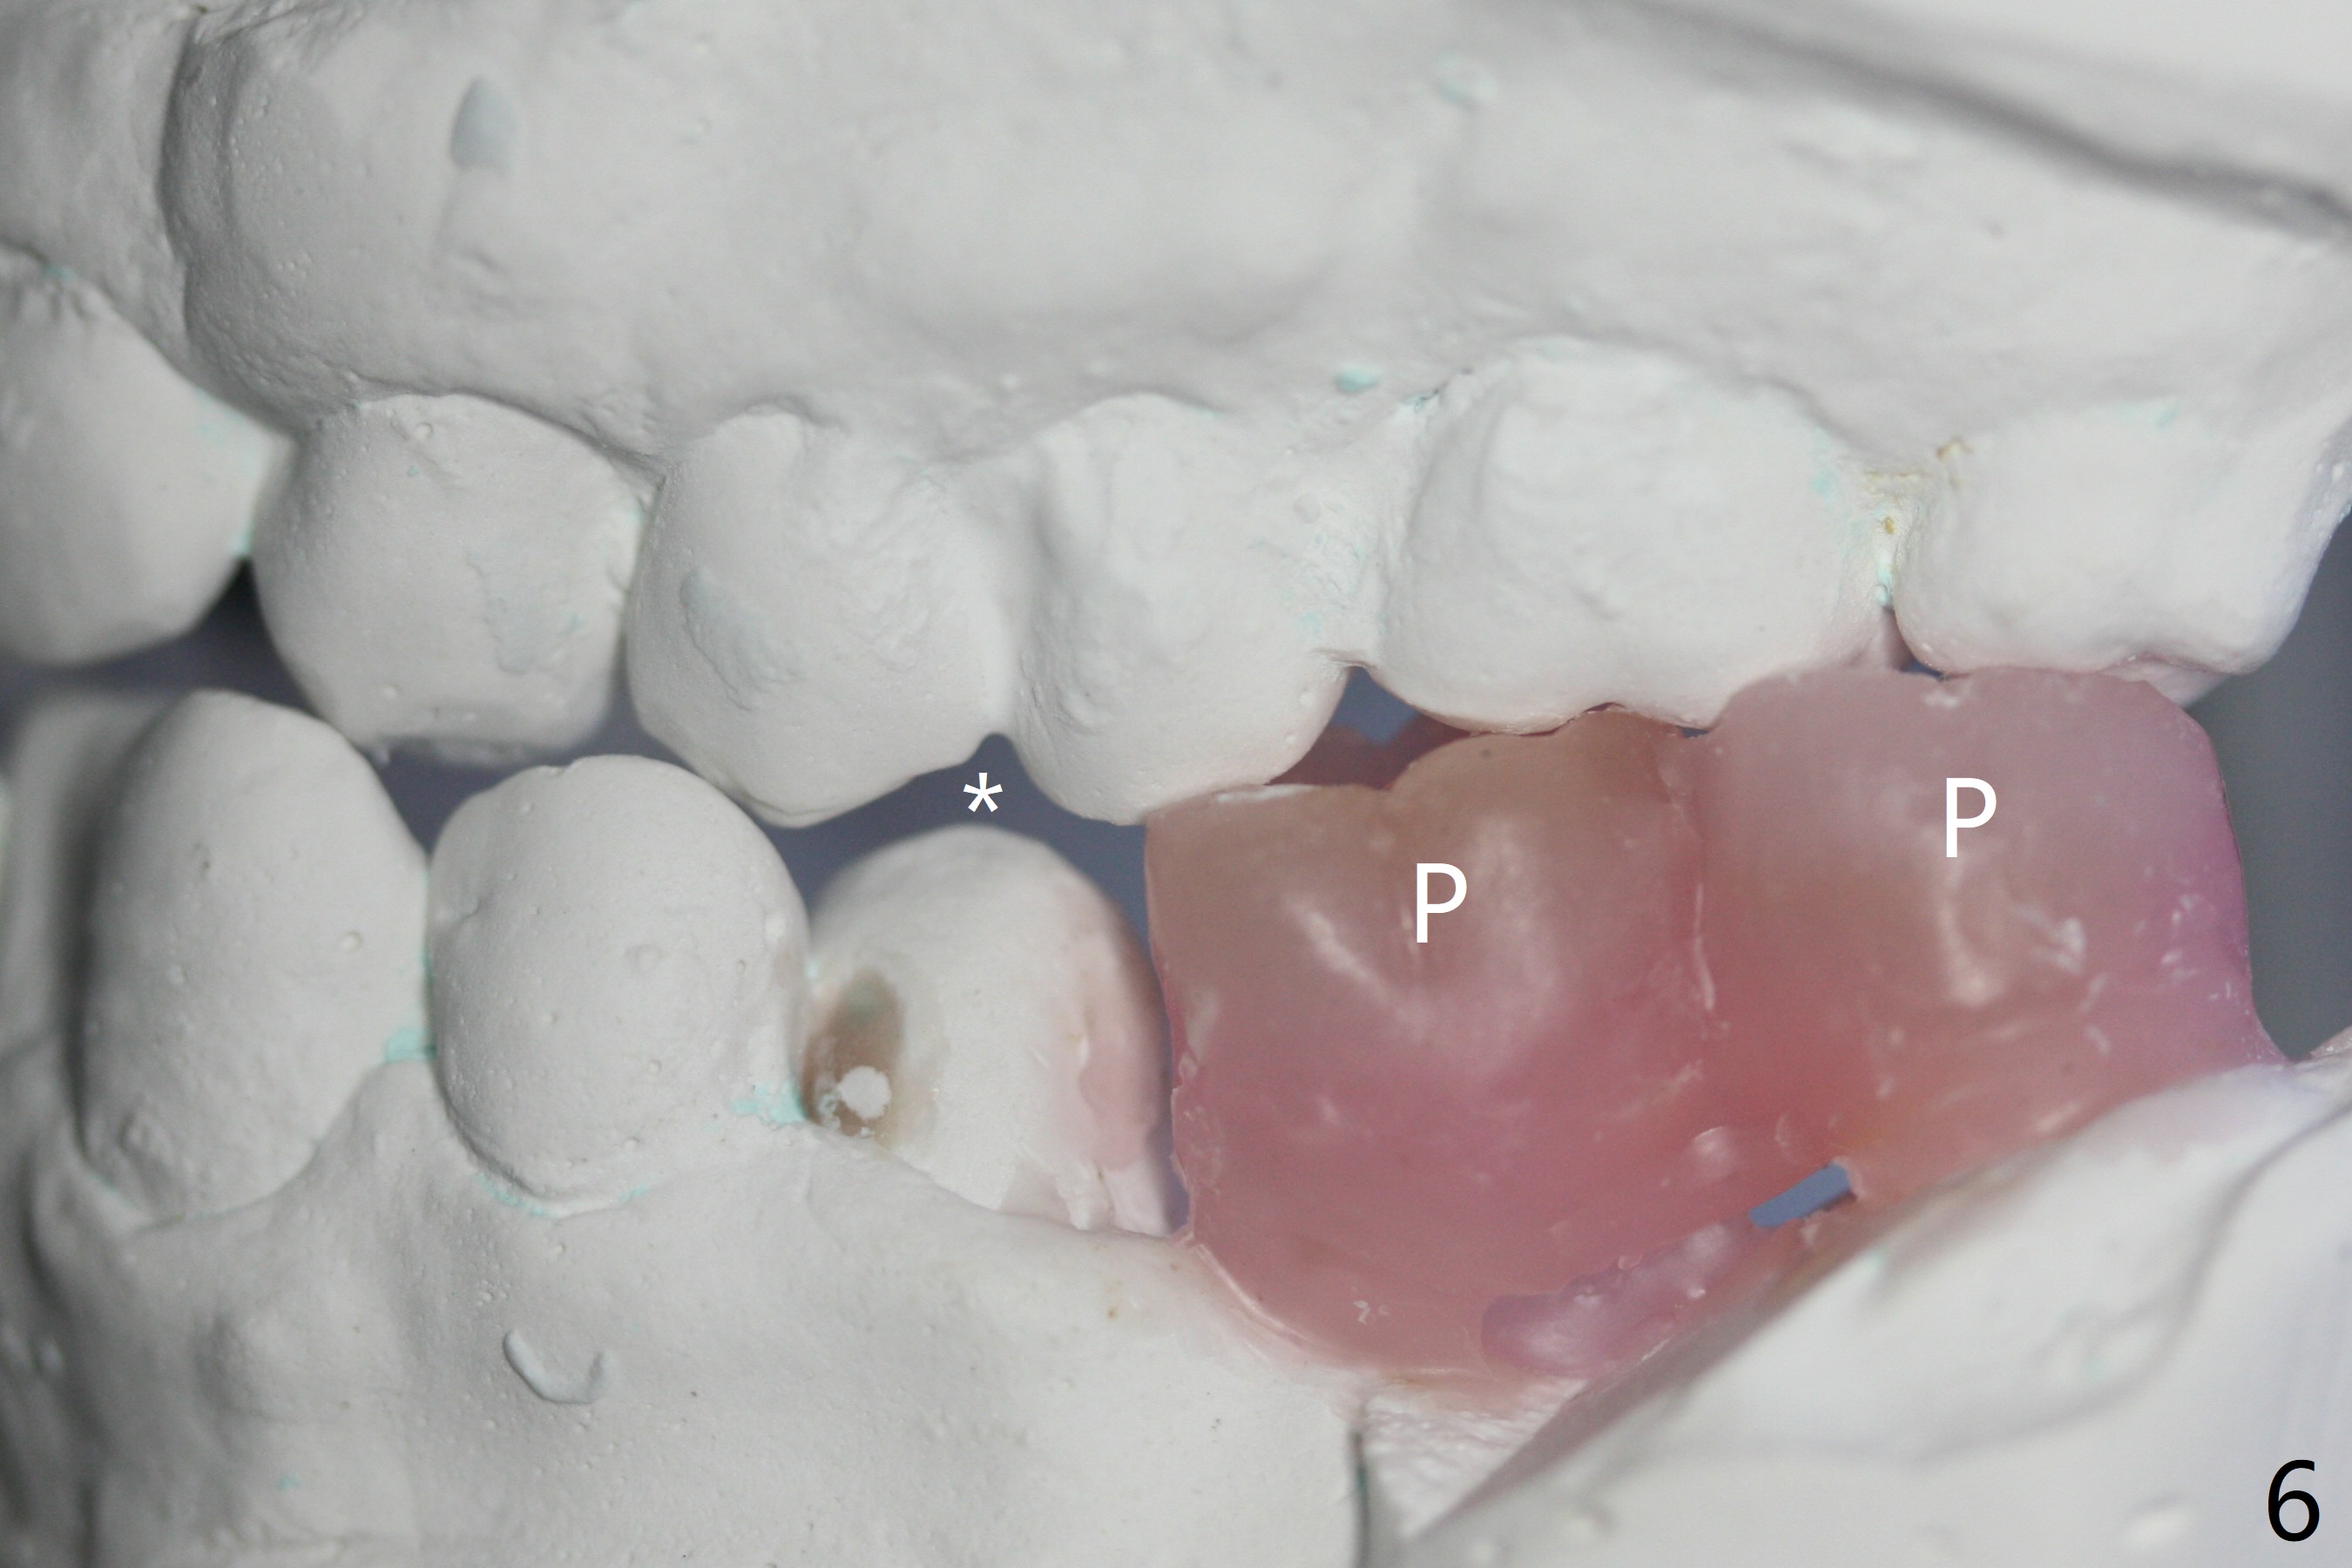

A 43-year-old man has poor dentition on the left: 1st molar missing, 2nd molar mesial inclination (Fig.1) and 2nd bicuspid lingual tilt (Fig.2). The latter is nonfunctional (Fig.3 (linguoposterior view). Two molar implants will be placed in a position so that their crowns will be in cross bite (Fig.4,5), the same occlusal scheme as the teeth #21 and 22. When these implants osteointegrate, the provisional crowns (Fig.6 P) will be supraocclusal so that there is clearance (*) for #20 to upright orthodontically (Fig.7-9). Moreover, these implants will be used anchorage as well as #21 and 22. Panoramic X-ray (Fig.1) and CBCT (Fig.10-12) show limited bone height at the sites of #18 and 19. It appears that 5x8 and 5.9x6 mm implants are appropriate with ridge reduction at #19.